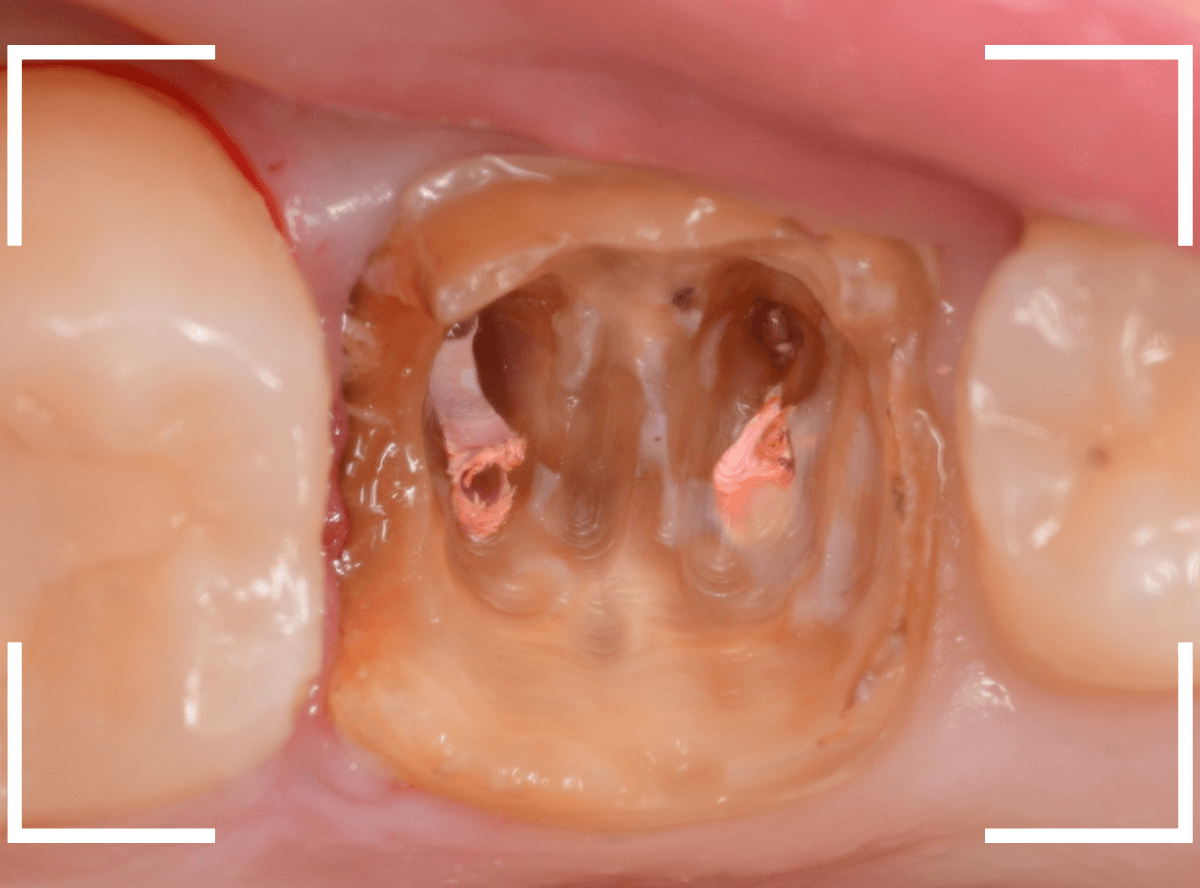

全ての虫歯を除去して綺麗になりました。

今回は、土台の型をお取りして、歯に優しいファイバーコアという素材で土台を作り直す事にします。